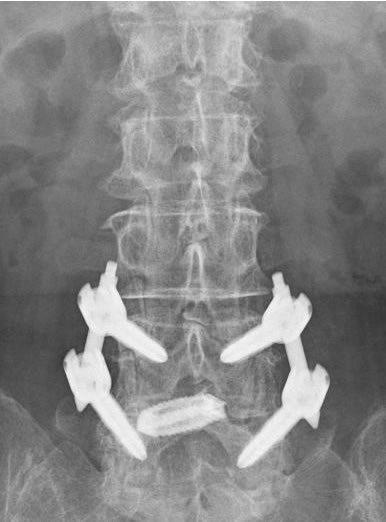

そのような患者さんには椎弓切除のみでは症状の改善が期待できないため、内視鏡下椎体間固定を行います。

内視鏡にて、移植骨、およびケージの挿入経路を作成します。

内視鏡腰椎椎体間固定術レントゲンと術後創部